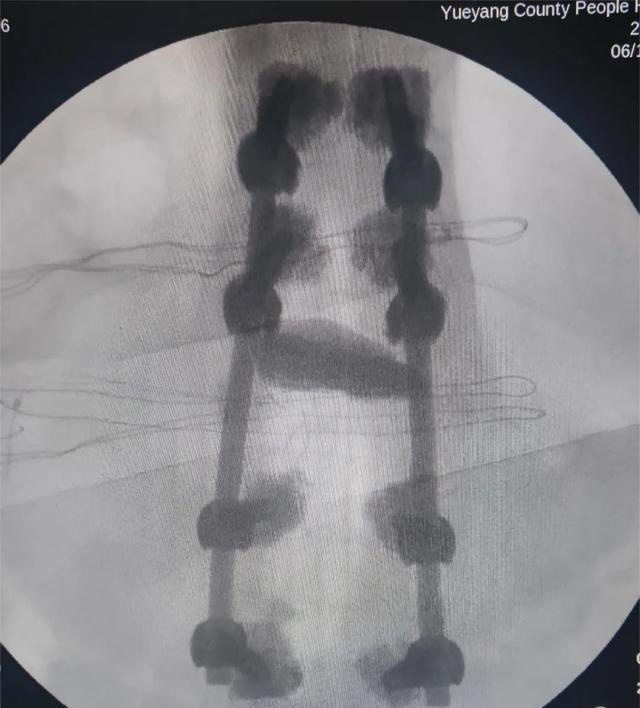

术中、术后影像(8钉2棒)

该手术可有效缓解腰背疼痛、改善伤椎 Cobb 角与椎体前缘高度,术后恢复快,强于PVP及PKP术式,是一种更安全、更有效的术式。

岳阳县人民医院神经脊柱外科已成功开展多例该类手术,患者一般在术后第二天、三天在绑着腰围的情况下可下地走路,疗效明显。